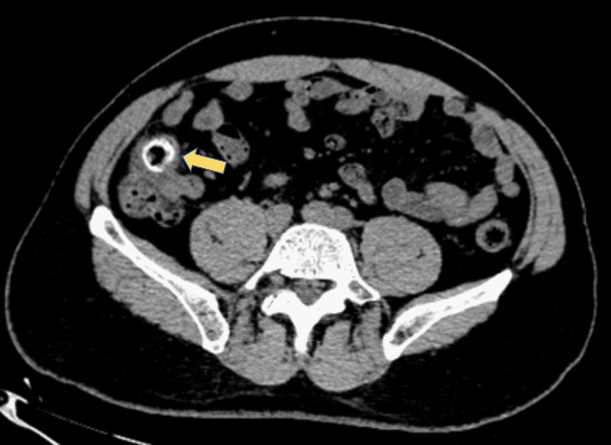

The computed tomography scan of abdomen showed about 20 mm X 20 mm circular high density shadow in right colon, which can be observed in colonic lumen but protruding out of the lumen. Colonoscopy (Figure 3) was also performed and the fecal impaction was identified in the cecal diverticulum above the ileocecal valve. The mucosa surrounding the diverticulum was hyperemic and edema. Than the fecalith was removed successfully with a foreign forceps under colonoscopy. The internal mucosa of the diverticulum was hyperemia, and no perforation was observed (Figure 4). The patient’s abdominal pain were relieved after endoscopic treatment. To prevent recurrence of the disease, surgical removal of the diverticulum was recommended but the patient was hesitant. There was no recurrence of abdominal pain and fecal impaction during 10 months follow-up.

Figure 3: Colonoscopy showed the fecal impaction in the cecal diverticulum above the ileocecal valve.